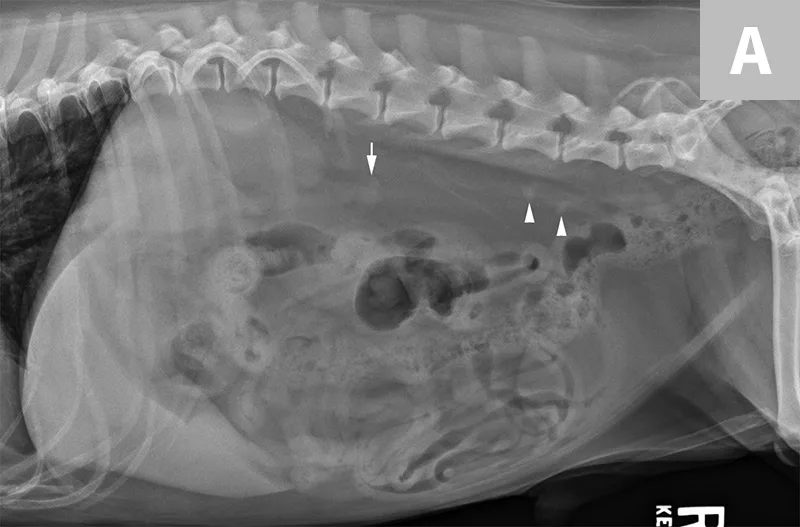

Lateral abdominal radiograph of a dog with 2 well-defined, oval mineral opacities superimposed over the retroperitoneal space caudal and dorsal to the kidneys (arrows). Based on the ventrodorsal projection (not shown), these calculi were likely to be associated with the right ureter.

Lateral abdominal radiograph of a cat with multiple, small, oval mineral opacities superimposed over the ventral aspect of the retroperitoneal space (arrows). These mineral opacities are arranged linearly extending from the caudal aspect of the kidneys to the level of the urinary bladder.